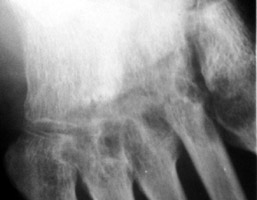

Rheumatoid Arthritis: Erosion 5th metatarsal head and base proximal phalanx

+++